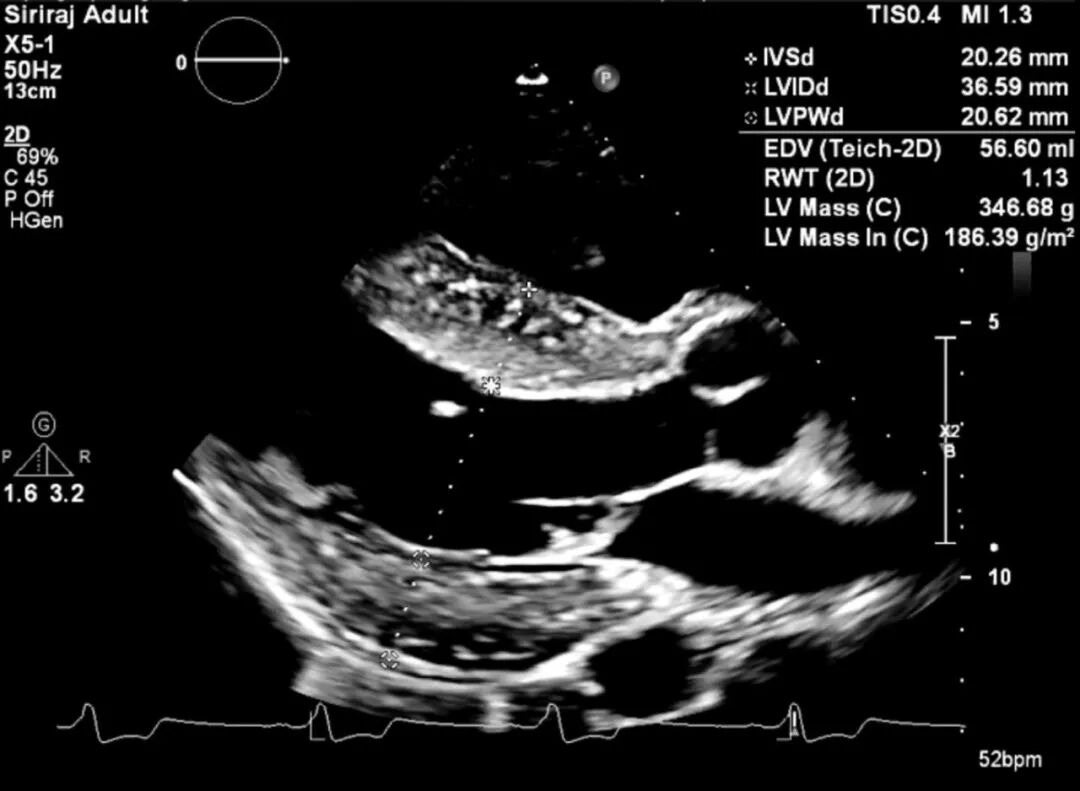

图3 经胸超声心动图(胸骨旁长轴视图)显示向心性左室肥厚,无显著心室内压差。